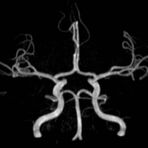

• intrakranielle Gefäße (Abklärung Verschluss, Stenose, Aneurysma)

MR-Angiografie (MRA)

Angiographie ohne Kontrastmittel

• MR-Angiografie ohne Kontrastmittel

• Time of Flight (TOF)-Angiographie

• Phasenkontrastangiographie (PCA). Geeignet zur Quantifizierung Stenose-/Insuffizienzgrad z.B. bei Herzklappen, falls echokardiographisch die Untersuchungsbedingungen eingeschränkt sind.

Je nach Fragestellung und Körperregion Gefäßdarstellung ohne Kontrastmittel bei Kontrastmittelunverträglichkeit oder terminaler Niereninsuffizienz möglich.

Ganzkörper Angiographie mit Kontrastmittel

• MR-Angiographie mit Kontrastmittel

• Erfassung arterieller und venöser Gefäße/Bypässe aller Körperregionen mit 3D-Rekonstruktion

• je nach klinischer Fragestellung zeitaufgelöste MR-Angiographie (4D-MRA) z.B. bei Frage arteriovenöse Fistel/ Shunt oder Darstellung Unterschenkelarterien vor geplanter Bypassoperation.